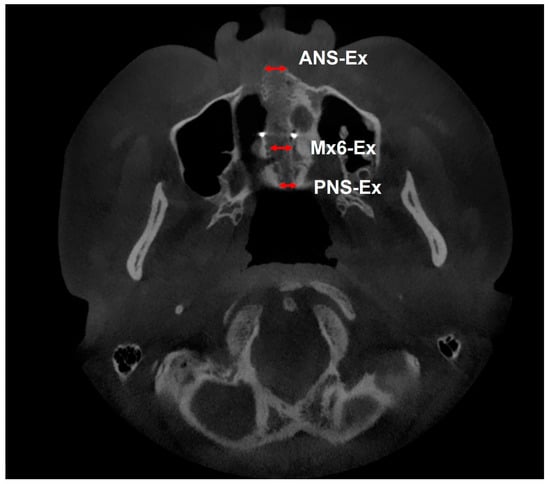

| ANS-Ex (Figure 3) | Amount of expansion of the midpalatal suture at the ANS site (mm). | Measurements are taken from a slice of the root apex of the palatal side of the left maxillary first molar in cross-section. |

| Mx6-Ex (Figure 3) | Amount of expansion of the midpalatal suture at the maxillary first molar area (mm). | |

| PNS-Ex (Figure 3) | Amount of expansion of the midpalatal suture at the PNS site (mm). | |

| ANS-Ex (mm) *† | 0 ± 0 | 4.39 ± 1.35 | 4.39 ± 1.35 | <0.001 *** | 0.012 * | - | 0.40 |

| Mx6-Ex (mm) *† | 0 ± 0 | 3.39 ± 0.95 | 3.39 ± 0.95 | <0.001 *** | - | 0.47 | |

| PNS-Ex (mm) *† | 0 ± 0 | 3.54 ± 0.98 | 3.54 ± 0.98 | <0.001 *** | - | 0.33 | |